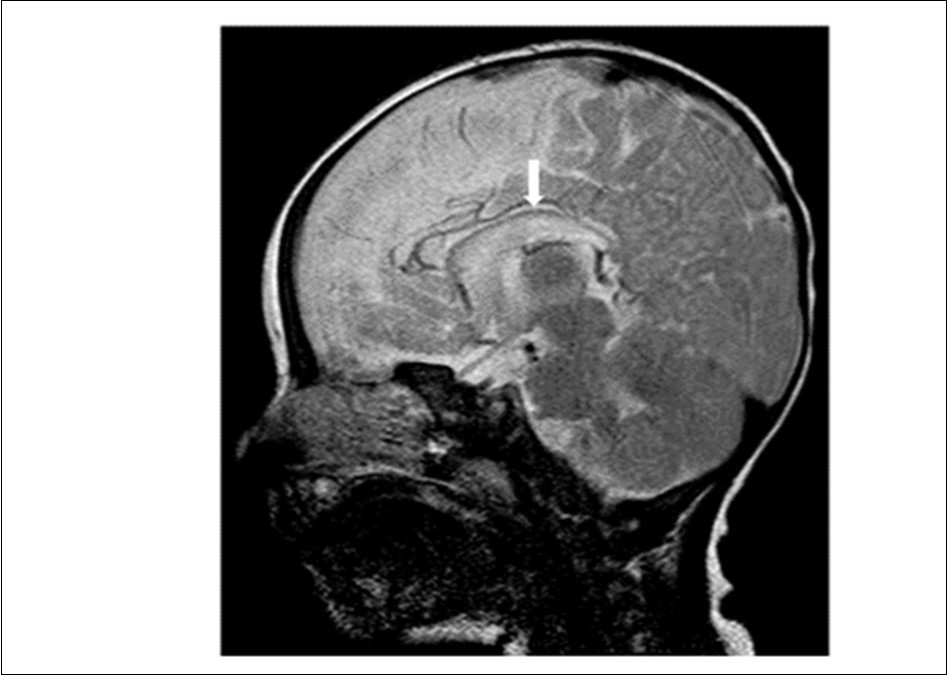

Cranial magnetic resonance imaging (MRI) was requested owing to the patient’s convulsion history and retarded development. The cranial MRI showed diffuse hypoplasia of the corpus callosum in the midline sagittal T2-weighted image (Figure 1 white arrow). T1-weighted imaging showed hypointensity due to delayed myelination of the genu of the corpus callosum (Figure 2, white arrow), which should normally appear hyperintense like the posterior limb of the internal capsule (Figure 2, blue arrow).

Figure 2.T1-weighted magnetic resonance image of the patient (7-month-old girl). The genu of the corpus callosum is hypointense due to myelination delay. In this age group, the genu of the corpus callosum should become hyperintense similar to the posterior limb of the internal capsule (blue arrow) due to myelination.

T1-weighted magnetic resonance image of the patient (7-month-old girl). The genu of the corpus callosum is hypointense due to myelination delay. In this age group, the genu of the corpus callosum should become hyperintense similar to the posterior limb of the internal capsule (blue arrow) due to myelination.